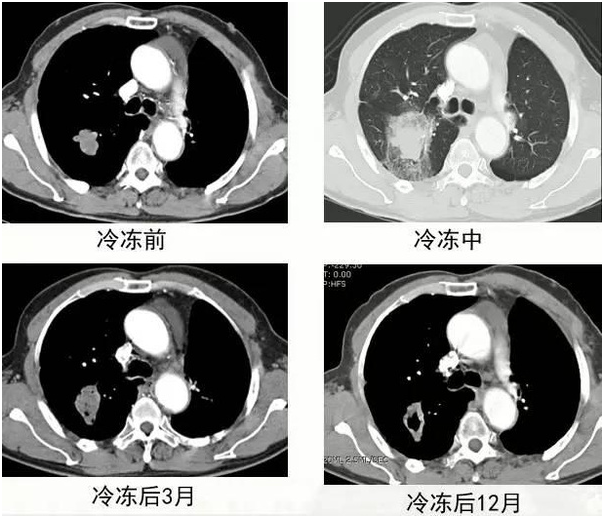

五、氩氦冷冻治疗

(男性,69岁,右肺鳞癌)

通过氩气的快速降温在胞内形成冰球,维持10-15分钟后用氦气进行升温,利用热胀冷缩的原理使肿瘤细胞破裂,从而达到治疗效果。适用范围: